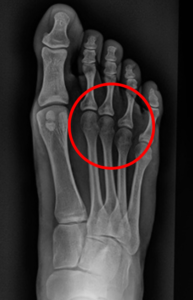

Prueba de rayos X: ¿Mejoran la alineación de los dedos?

El análisis de rayos X es una de las pruebas más reveladoras, ya que permite observar el impacto estructural de los separadores de dedos en el pie. Estos aparatos realmente consiguen una separación de los dedos aumentando el espacio entre ellos. Ahora bien, podríamos pensar que esa separación también se produce en el espacio entre las cabezas metatarsales.

Radiografía de paciente sin separador de dedos

Al hacer las radiografías con los separadores puestos observamos que mientras se separan los dedos, se produce un efecto cizalla y se aproximan los metatarsianos. Es decir, a nivel metatarsal generan un efecto parecido a llevar un calzado que nos comprimiese. Es importante resaltar que entre las cabezas metatarsales discurre el paquete vascular y nervioso que va a cada uno de los pies. Generar una disminución de ese espacio puede agravar ciertas patologías como el Neuroma de Morton.

Radiografía de paciente con separador de dedos

Bajo nuestro criterio, no tiene sentido que, si el objetivo de los separadores de dedos es que el pie se expanda, coloquemos algo que hace el efecto contrario en los metatarsianos.